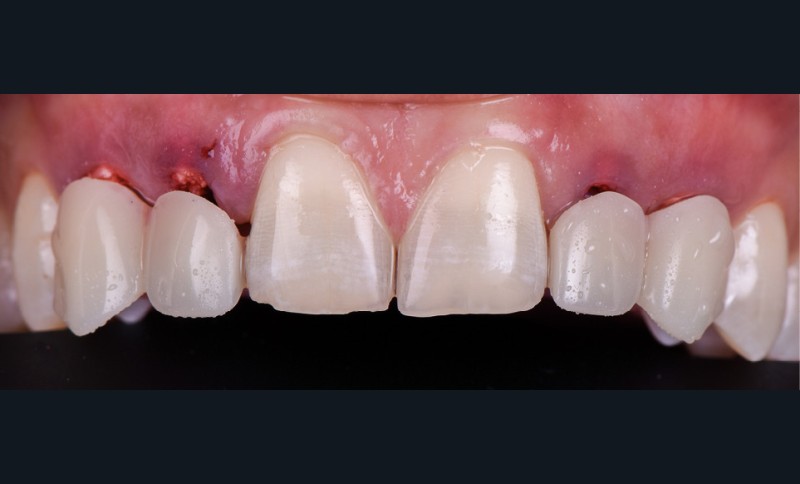

- pose des couronnes d’usage selon le protocole classique (fig. 9 et 10a) ;

- radiographies de contrôle (fig. 10b).